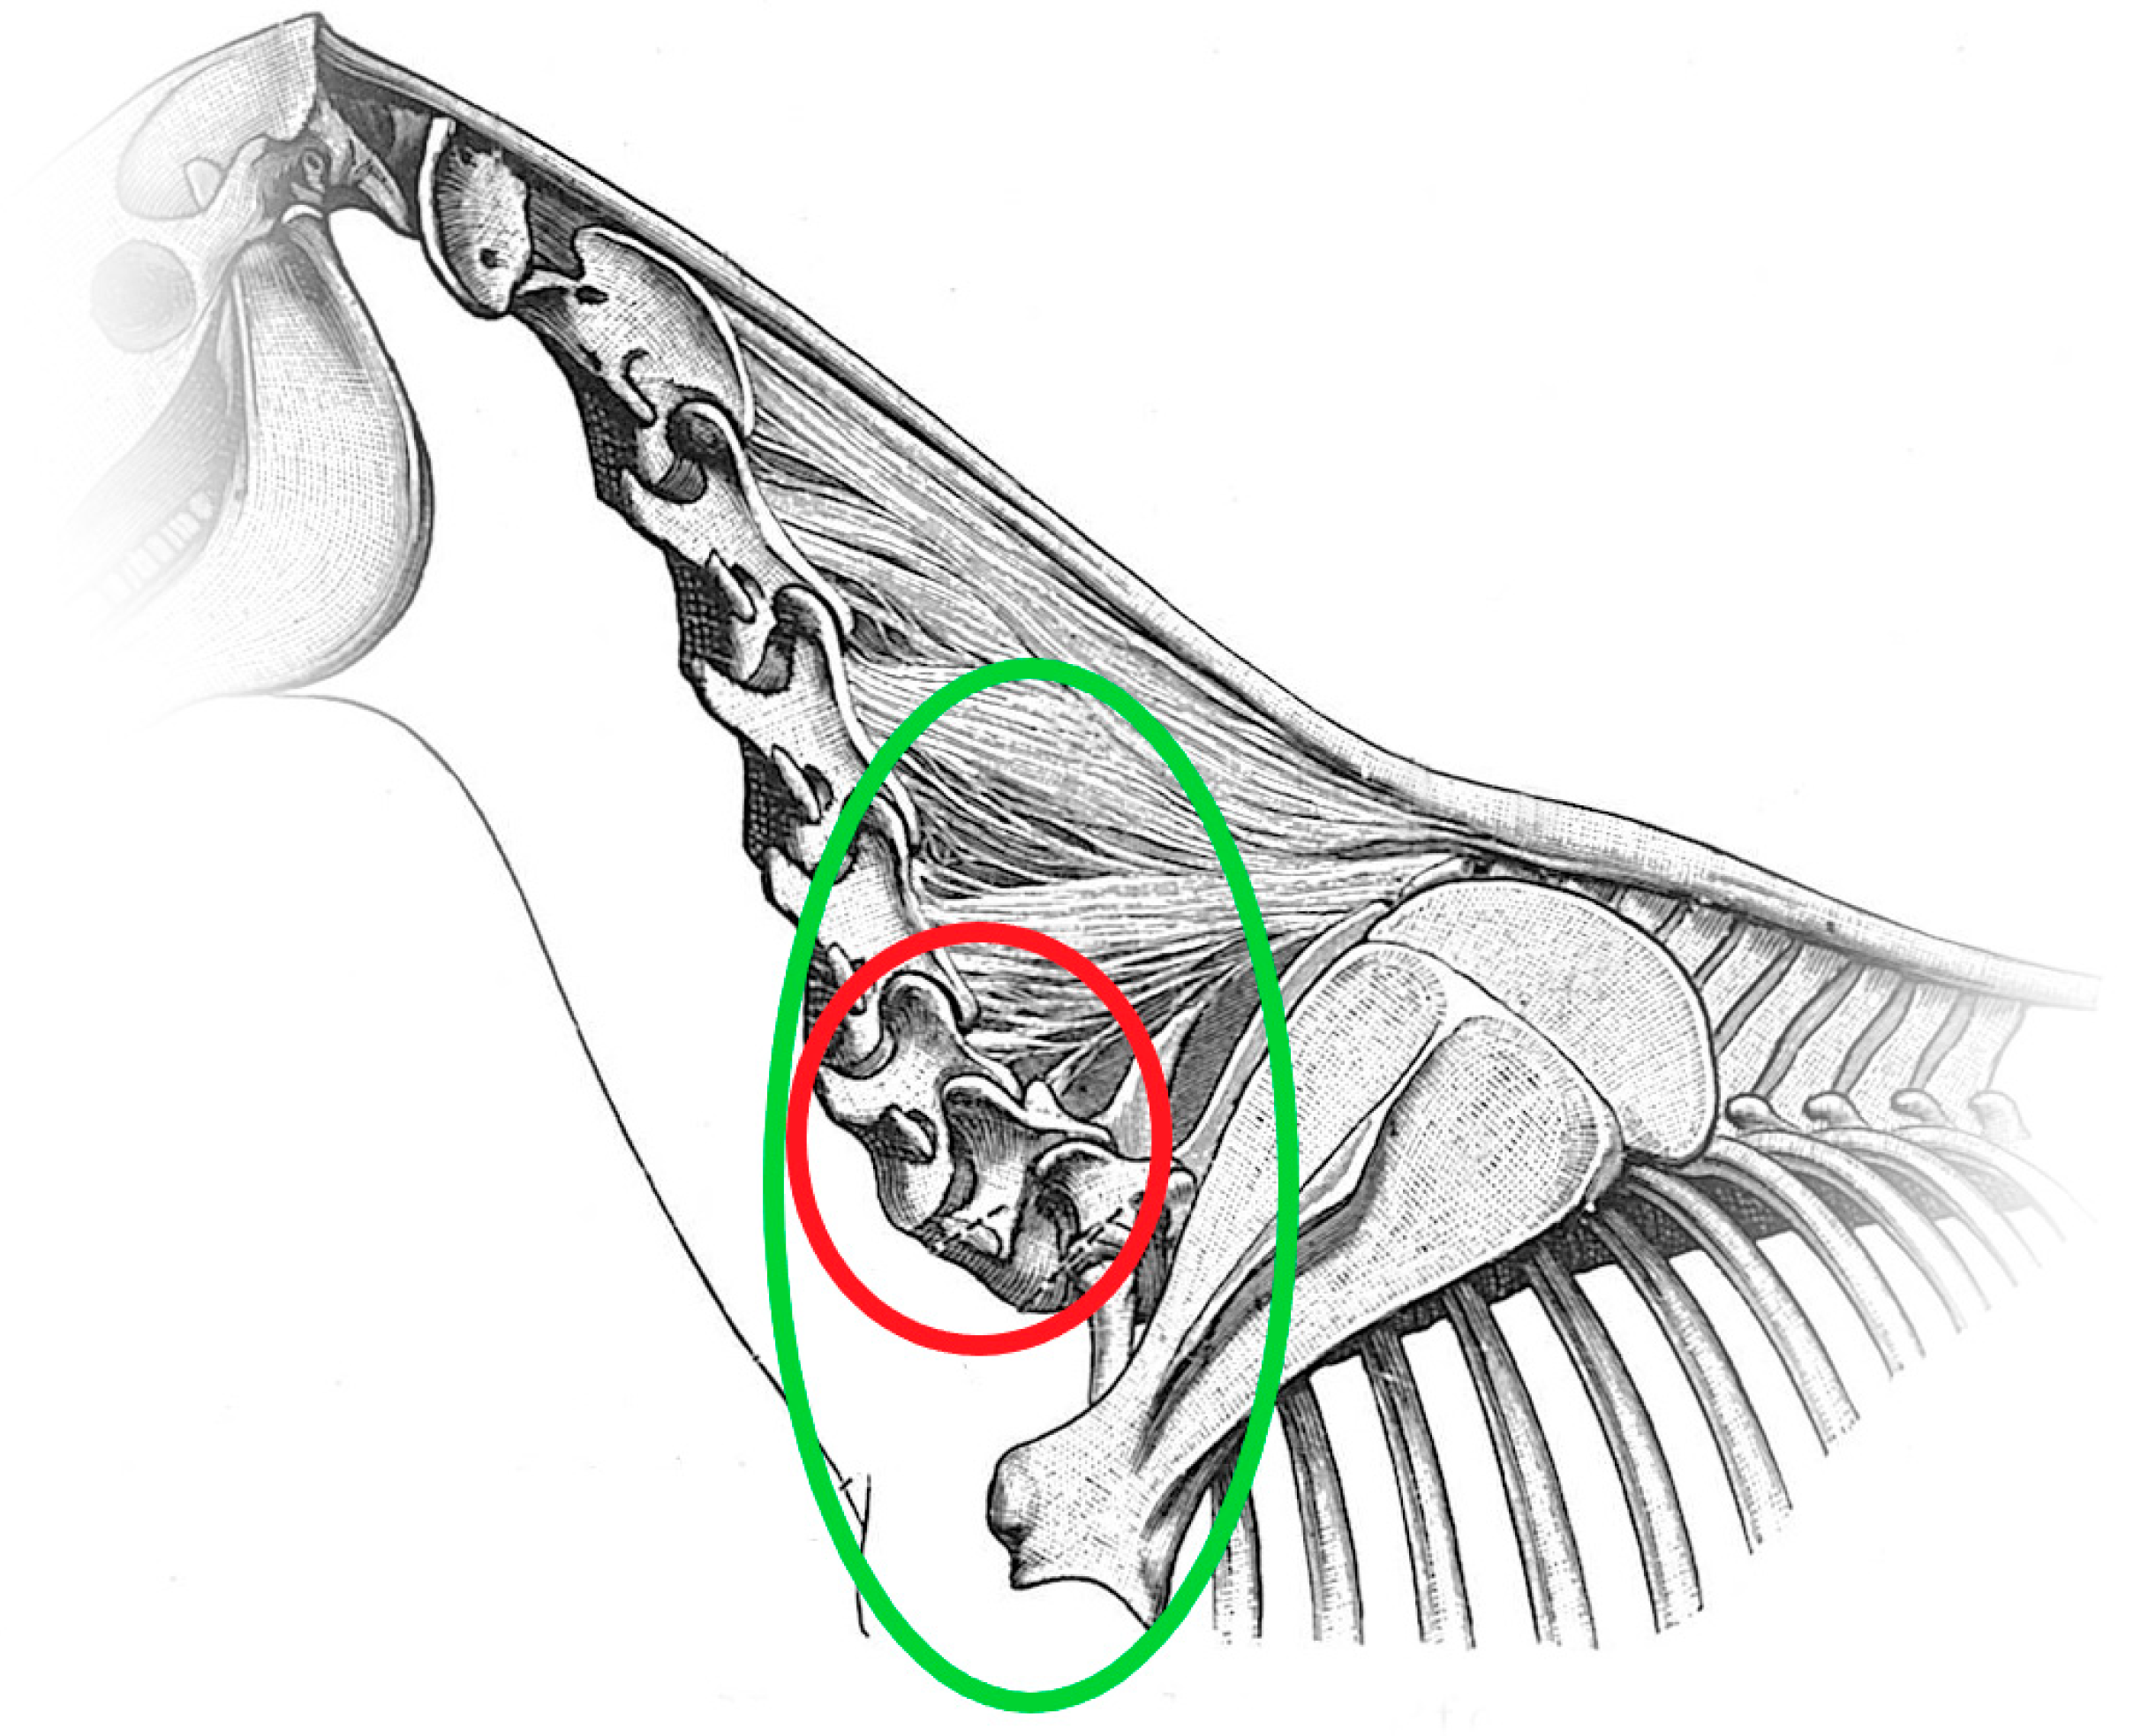

2.3. Radiographic Method

2.4. Classification System